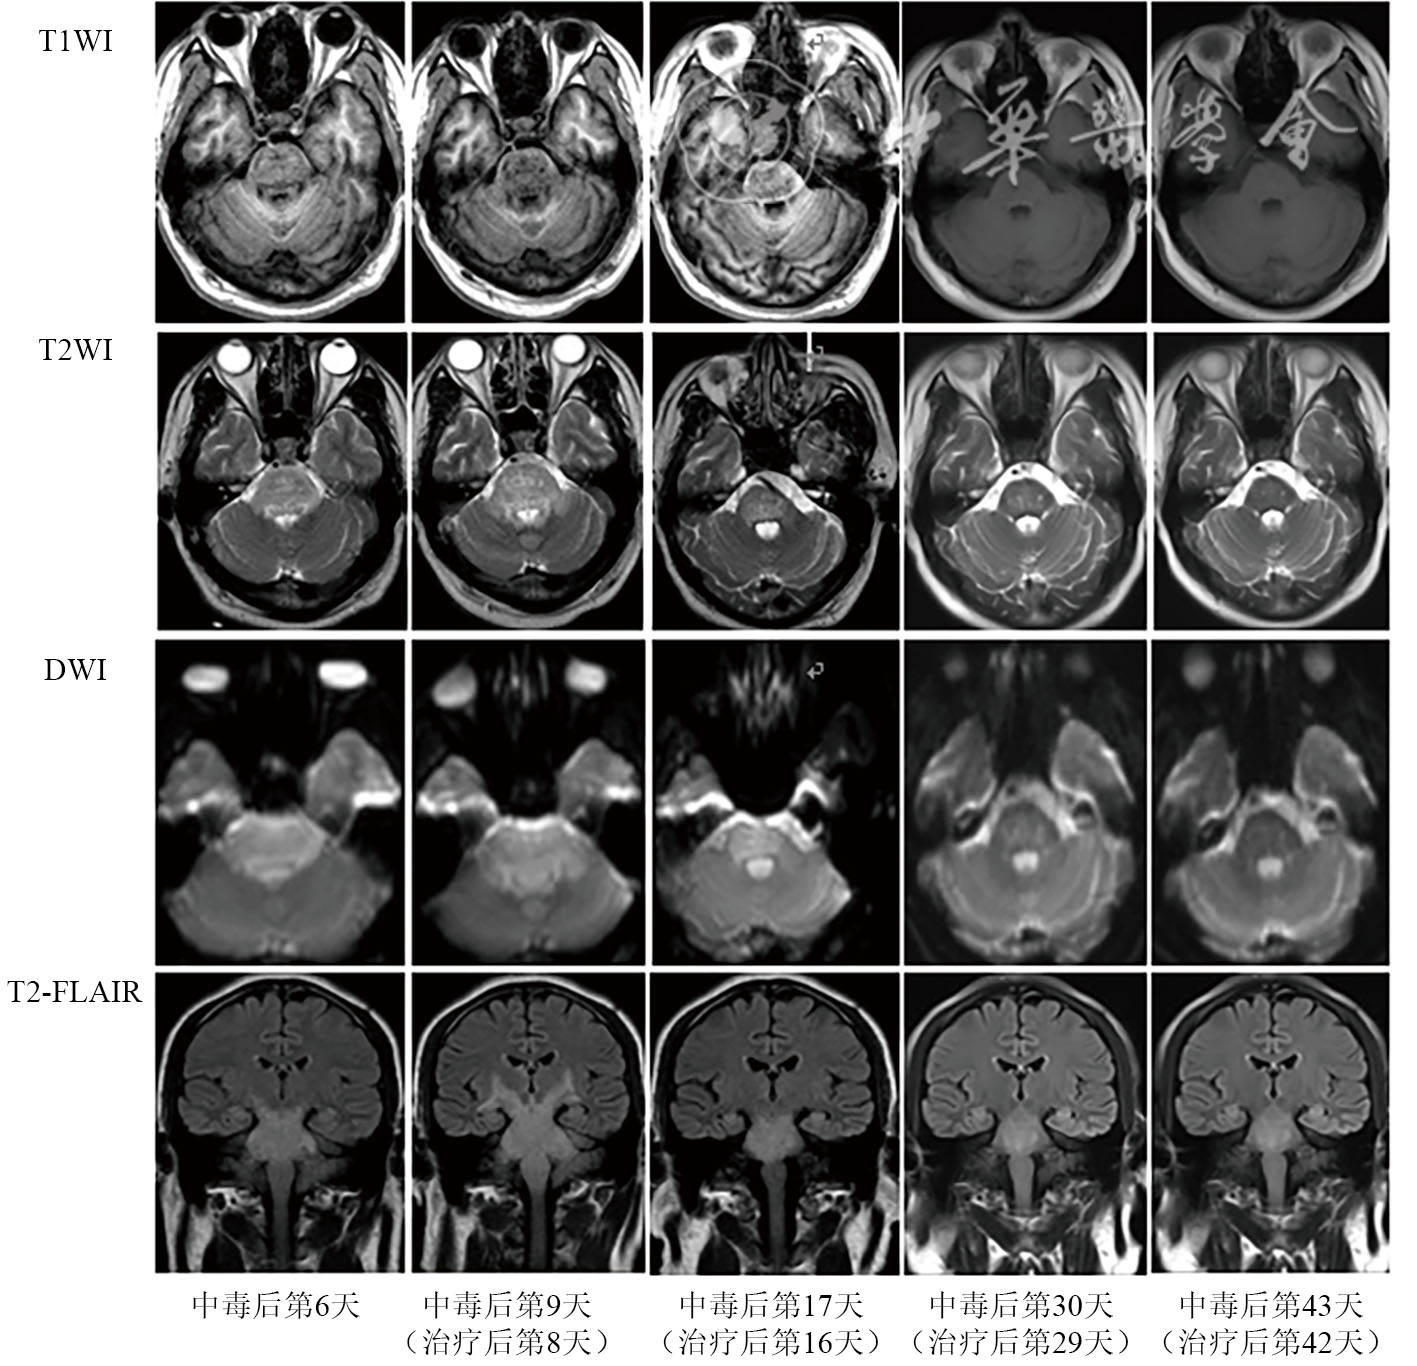

Ren Y, Guo F, Wang L. Imaging findings and toxicological mechanisms of nervous system injury caused by Diquat [J]. Mol Neurobiol, 2024, 61(11): 9272-9283.

Yu G, Jian T, Cui S, et al. Acute diquat poisoning resulting in toxic encephalopathy: a report of three cases [J]. Clin Toxicol (Phila), 2022, 60(5): 647-650.

Xing J, Chu Z, Han D, et al. Lethal diquat poisoning manifesting as central pontine myelinolysis and acute kidney injury: a case report and literature review [J]. J Int Med Res, 2020, 48(7): 300060520943824.

傅琳清, 叶梅萍, 王正阁, 等. 敌草快中毒性脑病一例报道及影像学分析 [J]. 中国CT和MRI杂志, 2023, 21(6): 187-188.

陈悦熙. 10例敌草快中毒性脑病患者的影像特征 [J]. 中华劳动卫生职业病杂志, 2022, 40(5): 362-365.